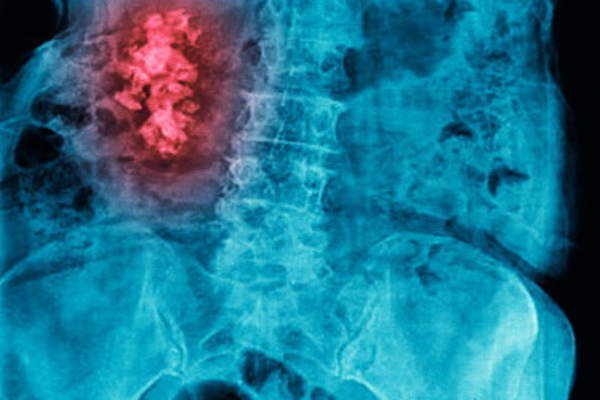

腹主动脉瘤(AAA)